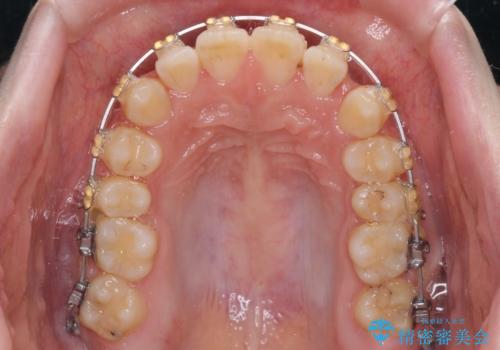

- 矯正装置

- 審美装置

- 大学病院にて装置を装着したものの、治療が十分に受けることができないとのことで転院をされた患者様です。

上顎歯列が前方にあり、口元が閉じにくくなっていたため、既に装着されている装置を使用して上顎歯列全体を後方に移動させていくこととしました。

舌の突出癖があり、それが原因で上下前歯に隙間ができていたため、改善のためのトレーニングを行うように指示をしました。